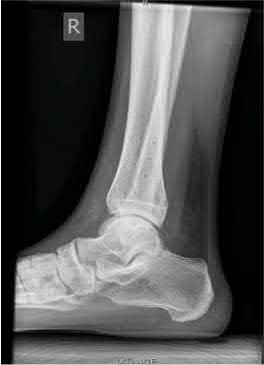

A 25-year-old male sustains an ankle fracture dislocation and undergoes open reduction and internal fixation. He returns to clinic five months following surgery complaining of continued ankle pain and instability with weight bearing. His immediate post-operative AP radiograph is seen in Figure A. Which of the following could have prevented this patient from developing persistent pain?

The patient presents with continued ankle pain and instability following open reduction and internal fixation. The radiograph in figure A demonstrates inadequate restoration of fibular length, likely leading to continued tibiotalar instability.

Illustration A demonstrates fibular malreduction with dislocation of the fibula anterior to the tibial incisura. Illustration B shows a comminuted fibula fracture along with a measurement of length from an intact fibula. The arc from the lateral process of the talus to the peroneal groove of the distal fibula is known as the "dime" sign and should remain unbroken if fibular length has been restored. Illustration C demonstrates the use of a push-pull screw and lamina spreader to regain length intraoperatively for a comminuted fibula fracture.

Chu and Weiner review management of malunions of the distal fibula. The authors state that restoration of fibular length, alignment and rotation leads to reduction of the talus, provides a buttress to talar motion in the setting of an incompetent deltoid, and allows the syndesmotic ligaments to heal at the appropriate tension.